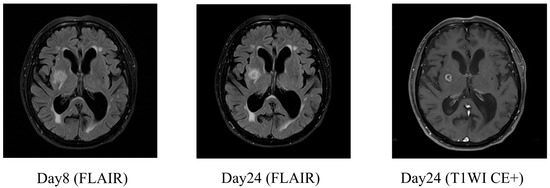

2.1. Case 1